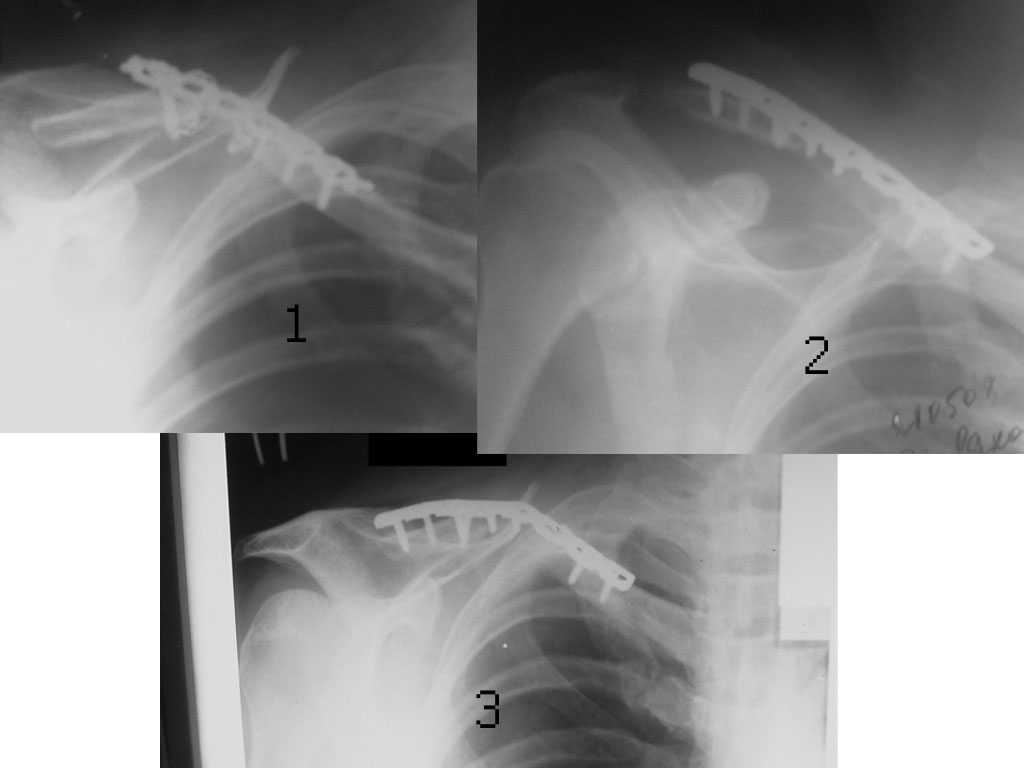

Уважаемые коллеги. Помогите с тактикой дольнейшего лечения несросшегося перелома ключицы. В отделение поступил больной, оперированный 2 мес. назад по поводу оскольчатого перелома средней трети правой ключицы. Перелом несросшийся, фиксатор несостоятелен, имеется смещение, угроза перфорации кожи. Рис. 1 Намми произведен реостеосинтез ключицы пластиной с угловой стабильностью, с замещением деффета диафиза ключицы костным аутотрансплантатом. Рис. 2 Через 5 мес. трансплантат рассосался, повторное смещение, несостоятельность импланта. Рис. 3Ваше мнение,что делать?

Идеальным вариантом представляется резекция ложного сустава, замещение образовашегося дефекта васкуляризированным малоберцовым трансплантатом и интрамедуллярный блокированный остеосинтез.

В условиях российской бедности мы делали свободным "столбиком" из малоберцовой и неблокированным штифтом. Результат был хороший (фото).